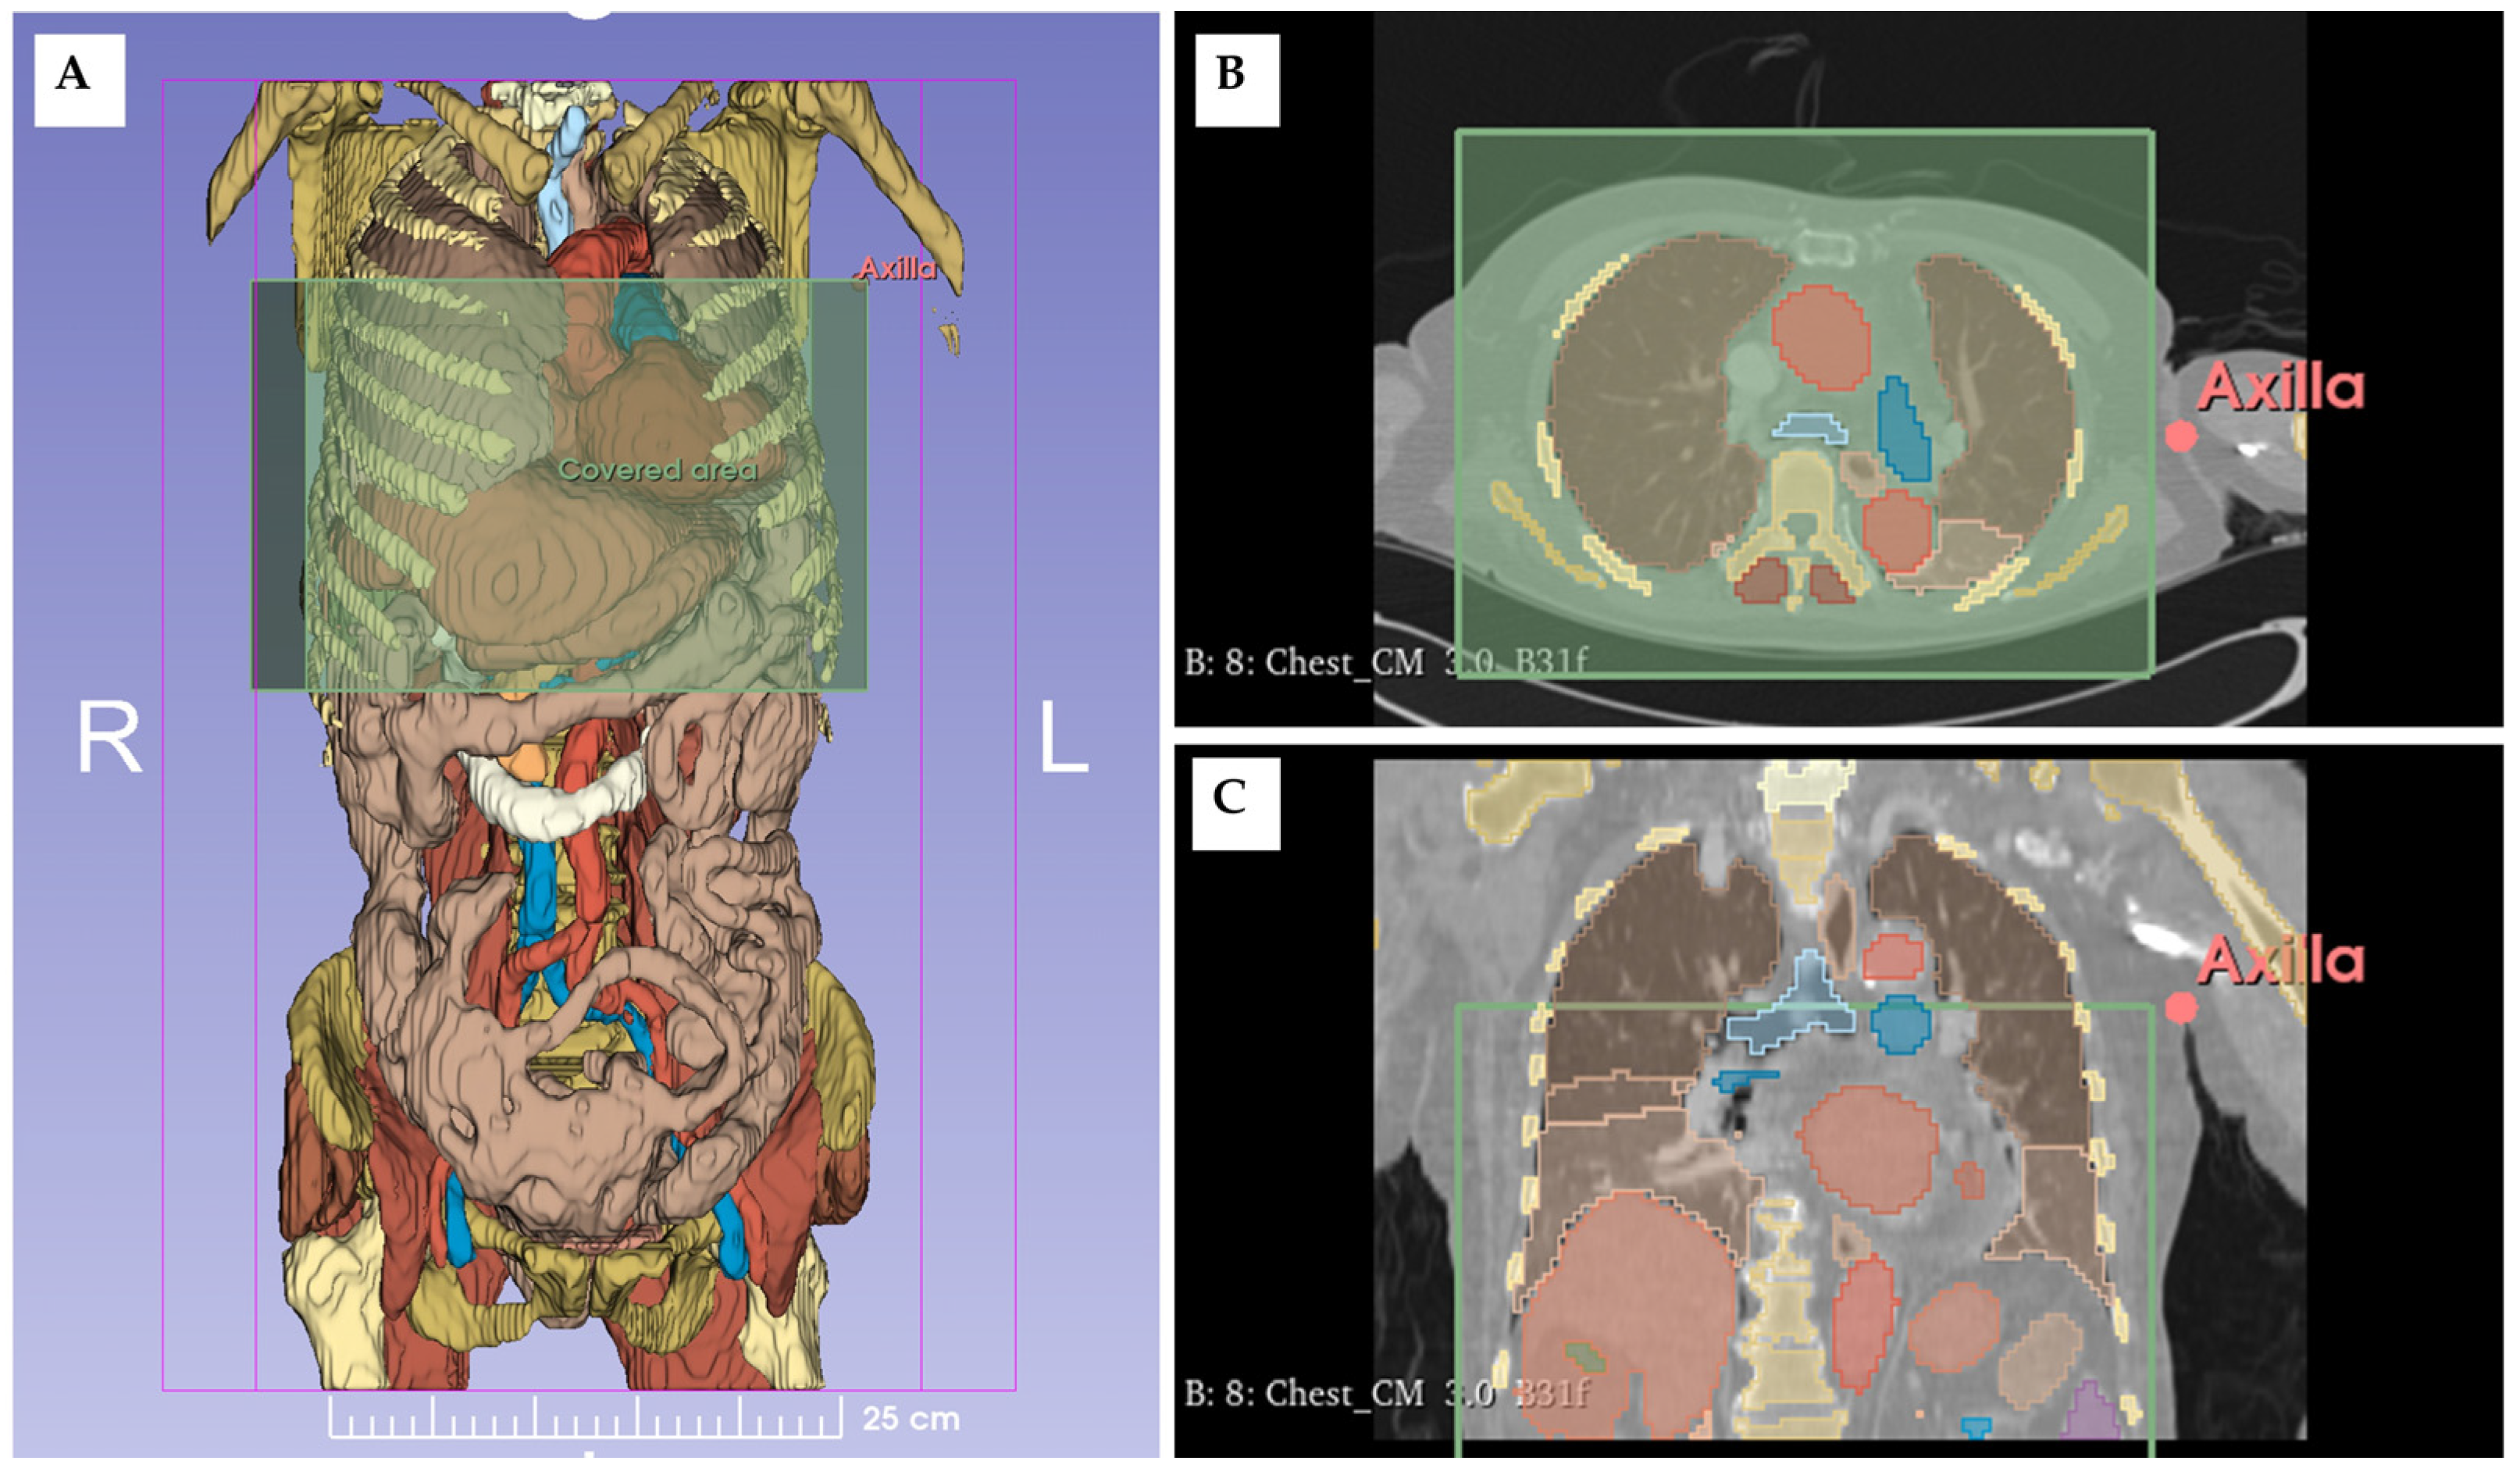

4.2. Imaging-Based Position Optimization for LDB